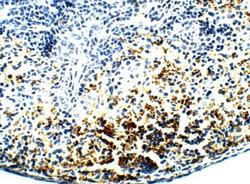

- Submitted by

- Novus Biologicals (provider)

- Main image

- Experimental details

- Immunohistochemistry-Paraffin: PAR2 Antibody [NBP2-11250] - 1:100 dilution in IHC blocking buffer. DAB (brown) staining and Hematoxylin QS (blue) counterstain. 40X magnification.